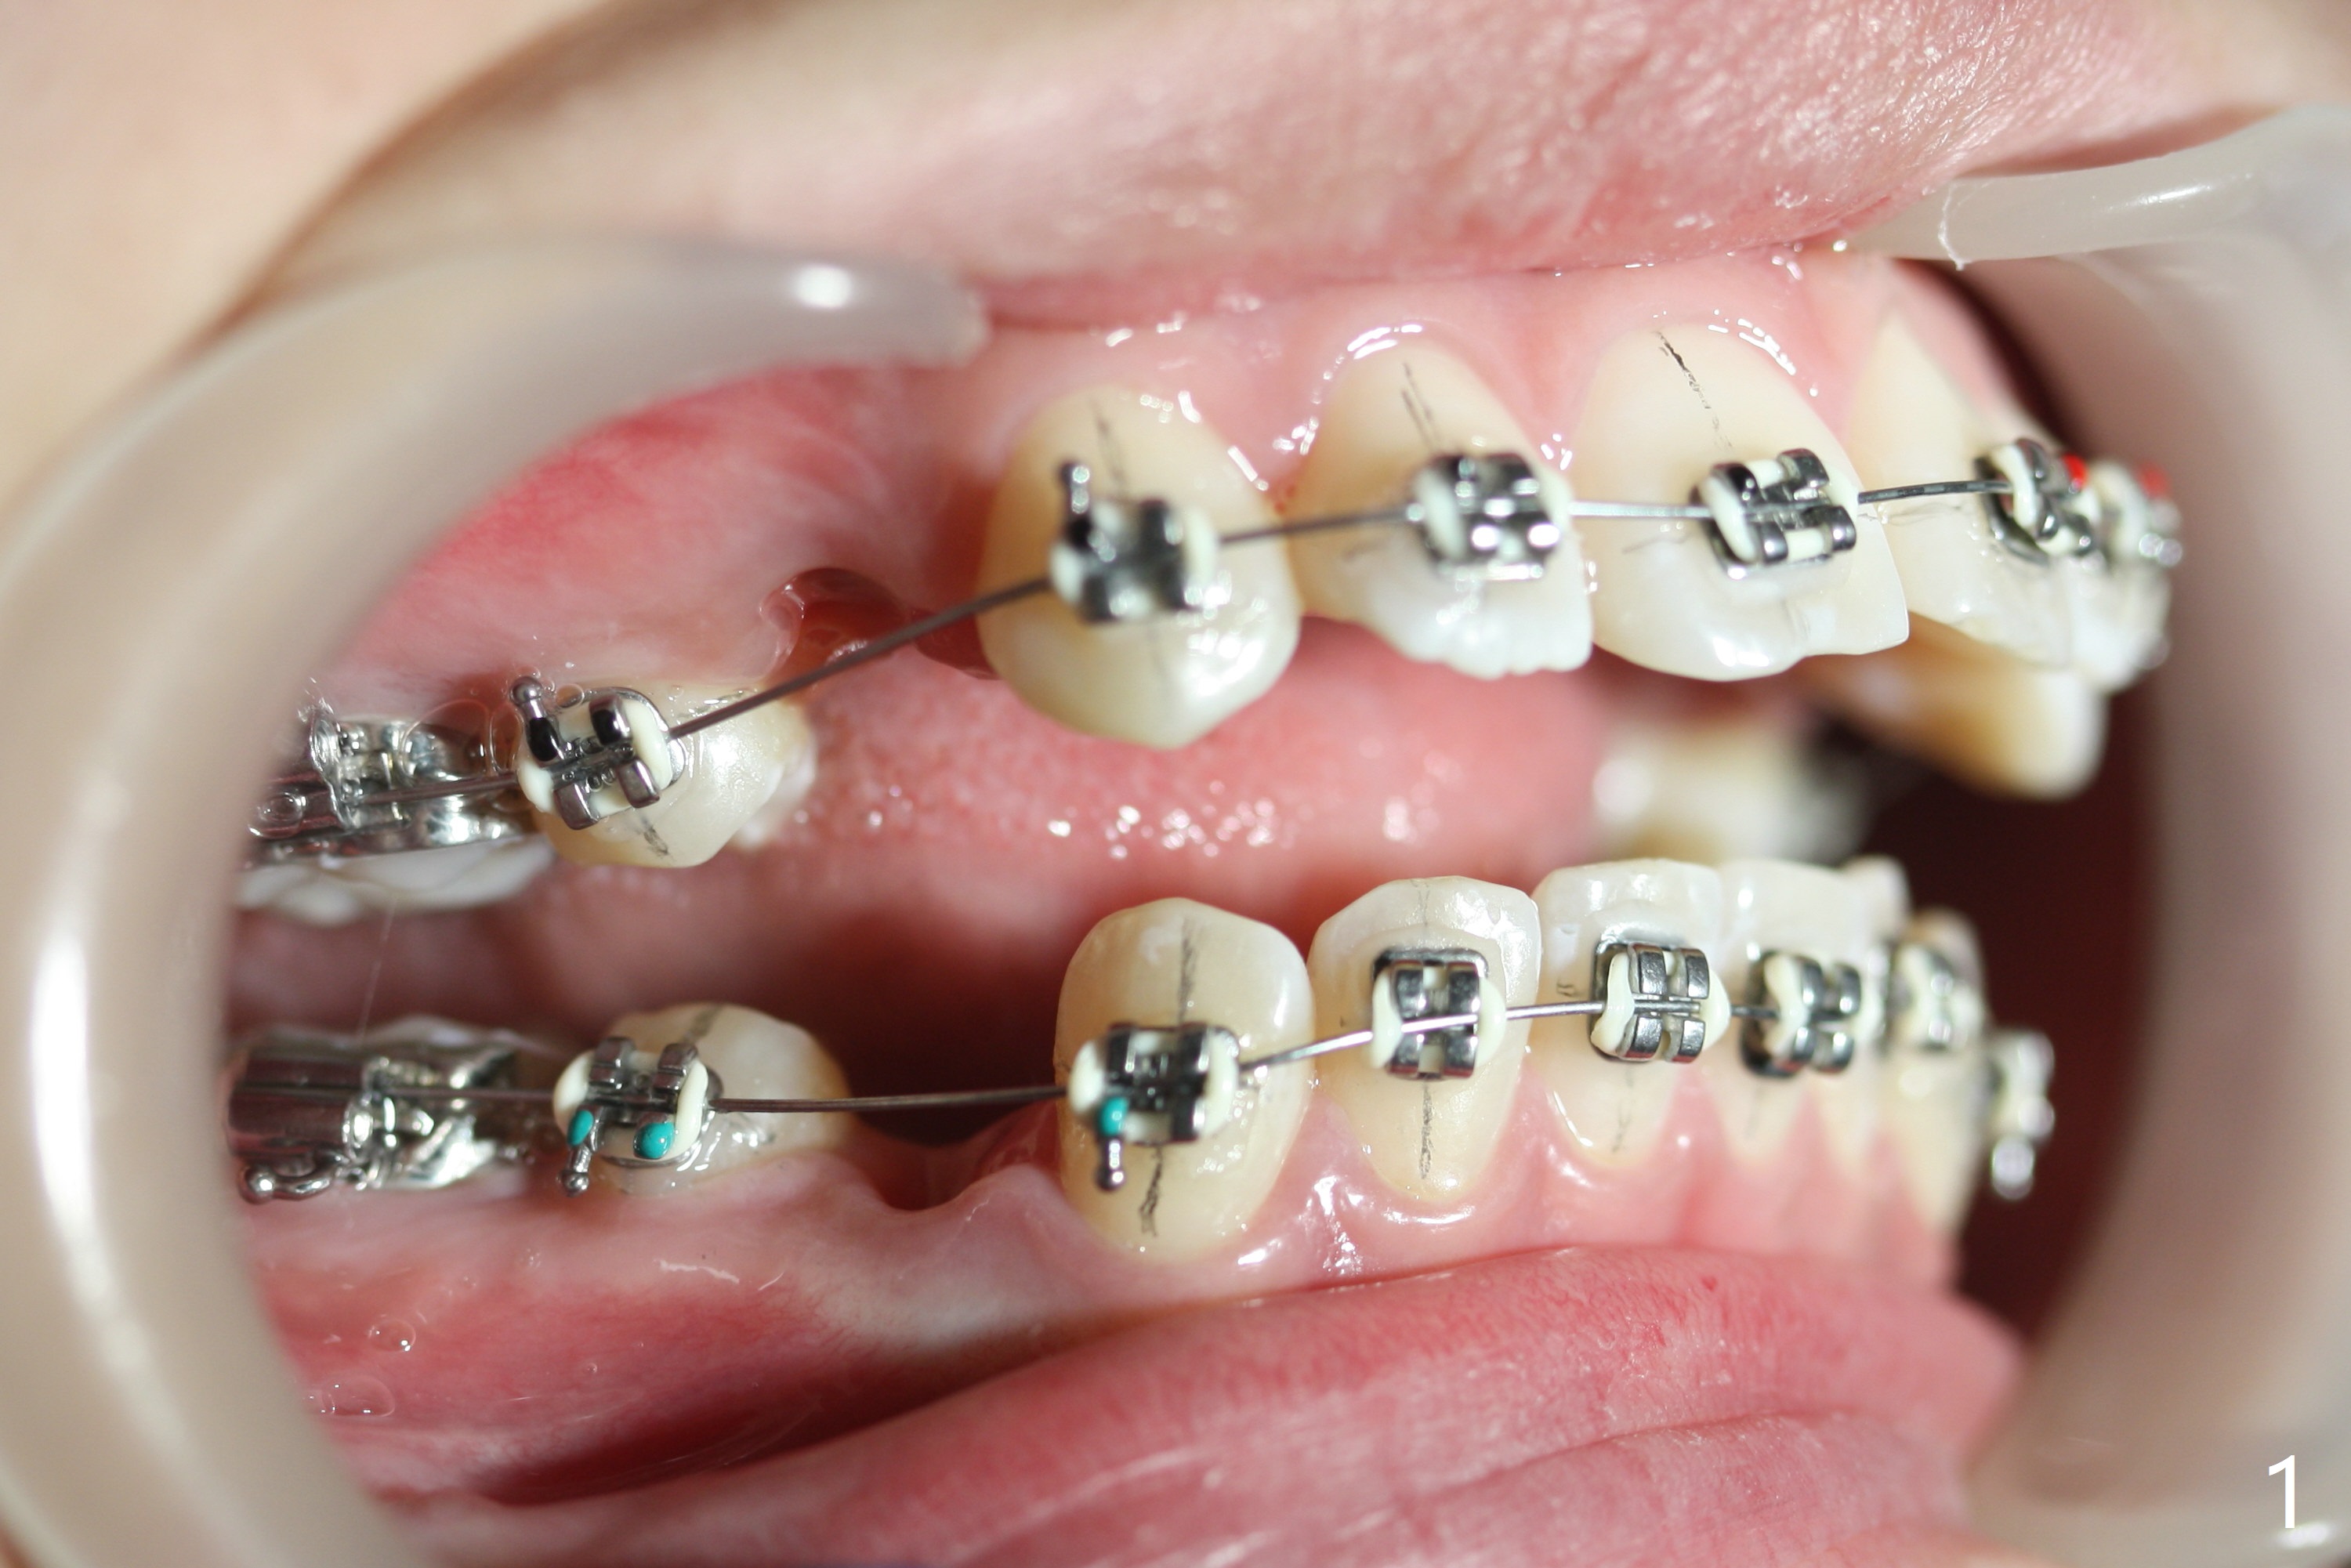

Two weeks post extraction of 4 bicuspids, brackets and bands are placed in 20 teeth (Fig.1-3, 14 niti). No bands are placed at 7s because of short crowns and tight contacts. When 16x16 wires are used, start Class II retraction. The latter is initiated with elastics when 18 ss wires are placed (Fig.4,5). U3s have been distalized with closed springs for 3 months (Fig.6,7). U2s are close to distalization 13 months post banding, 3.5 months post posted wire (Fig,8,9) with overjet (Fig.10). Class II retraction is re-initiated. When the upper incisors are retracted, the anterior overjet remains large. It appears that U6s have been retracted anterior, as indicated by the space between U6/7 (Fig.11), because of no use of U7s as anchors. Brackets are just placed with 18 niti arch wire. They will be retracted distal using the rest of the upper teeth and lower teeth (using Class II retraction) as anchor. There is root resorption of the upper anteriors 2 years 1 month post banding (Fig.12,13).